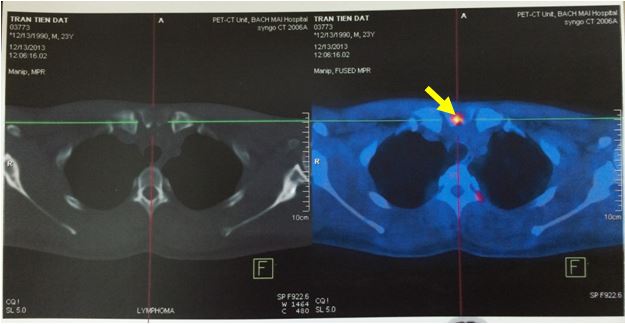

Hình ảnh hạch thượng đòn còn lại sau 4 đợt hóa chất R CHOP.

Sau khi được chụp PET/CT, có điều đặc biệt ở bệnh nhân này là tổn thương hạch ổ bụng phát hiện trên CT lại hoàn toàn không tăng hấp thu FDG, mà bệnh nhân lại được phát hiện thêm một tổn thương tăng hấp thu FDG bất thường ở đầu xương ức. Các vị trí khác trong cơ thể không có tăng hấp thu FDG bất thường.

Tổn thương đầu xương ức tăng hấp thu FDG( tổn thương này hoàn toàn không phát hiện được trên CT thường).